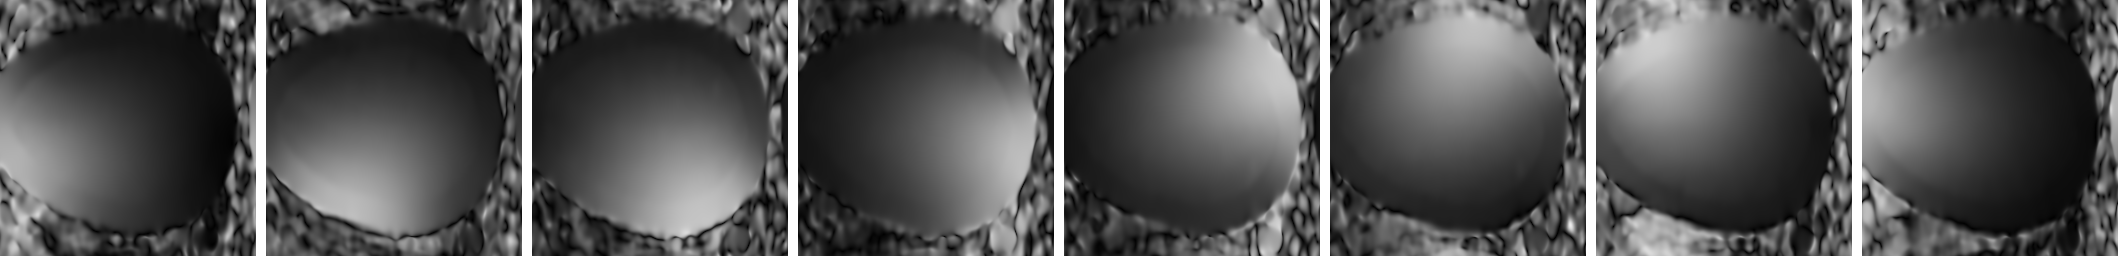

Refer to caption

Figure 4: Maps of standard deviation of noise σ(𝐱)subscript𝜎𝐱\sigma_{\mathcal{R}}({\bf x}) in the final image: (a-c-e): Theoretical values. (b-d-f): Estimated from samples. (a-b) Synthetic Sensitivity Map with no correlation. (c-d) Synthetic Sensitivity Map with correlation between coils. (e-f) Real sensitivity map with correlation between coils.

The second and third experiments deals with the non homogeneous spatial layout of the noise and the influence of the sensitivity map over the final noise distribution. Visual results are depicted in Fig 4. For the synthetic maps, when no correlations are considered, since l|Cl(𝐱)|2=1subscript𝑙superscriptsubscript𝐶𝑙𝐱21\sum_{l}|C_{l}({\bf x})|^{2}=1 for all pixels, the final variance of noise will not depend on the position 𝐱𝐱{\bf x}. Therefore, in this particular case σ2(𝐱)=σ2subscriptsuperscript𝜎2𝐱subscriptsuperscript𝜎2\sigma^{2}_{\mathcal{R}}({\bf x})=\sigma^{2}_{\mathcal{R}}. The estimated values in Fig 4-(b) show a noise pattern that slightly varies around the real value (note the small range of variation). In this very particular case, the noise can be considered to be spatially stationary, and the final image (leaving the correlation between pixels aside) is equivalent to one obtained from a single-coil scanner.

When correlations are taken into account, even using the same synthetic sensitivity map, results differ. In Fig. 4-(c), the theoretical value shows that the standard deviation of noise of the reconstructed data is not the same for every pixel, i.e., the noise is no longer spatial-stationary. The center of the image shows a larger value that decreases going north and south. So, in this more realistic case, the σ2(𝐱)subscriptsuperscript𝜎2𝐱\sigma^{2}_{\mathcal{R}}({\bf x}) will depend on 𝐱𝐱{\bf x}, which can have serious implications for future processing, such as model based filtering techniques. The estimated value in Fig. 4-(d) shows exactly the same non-homogeneous pattern across the image.

In the last experiment, Fig. 4-(e) and Fig. 4-(f), a real sensitivity map is used, and correlation between coils is also assumed. Again, the noise is non-stationary. To increase the dynamic range of the images, the logarithm has been used to show the data.